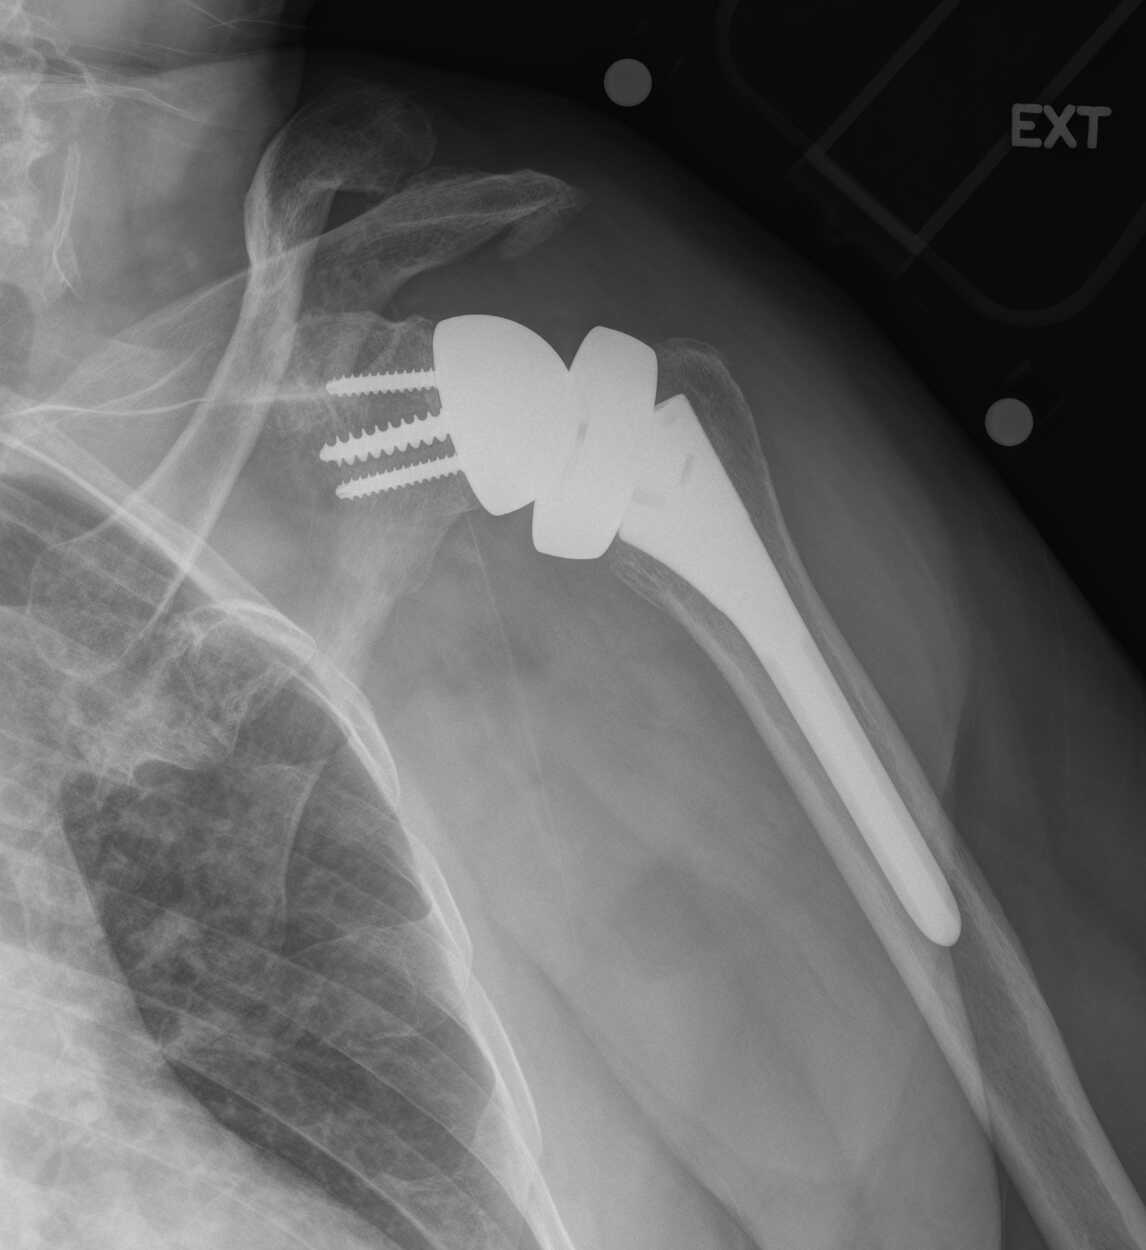

Reverse Total Shoulder Arthroplasty What Is A Shoulder Replacement Called How long does it take to recover? Total shoulder replacement, also known as total shoulder arthroplasty, is the removal of portions of the. In shoulder replacement surgery, the damaged parts of the shoulder are removed and replaced with artificial components, called a prosthesis. The specific type of shoulder. Learn more about the procedure, risks, recovery time, and what to. Total. What Is A Shoulder Replacement Called.